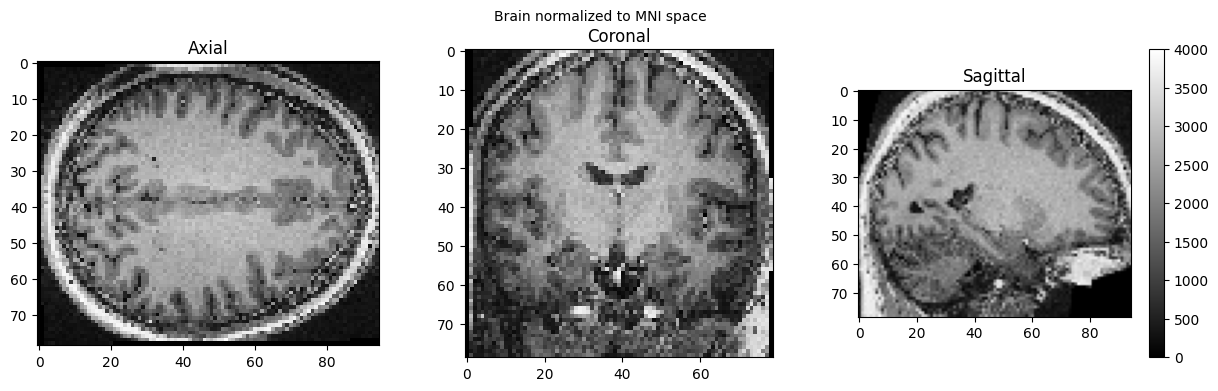

import nipype.interfaces.spm as spm

norm12 = spm.Normalize12()

norm12.inputs.image_to_align = './sub-01_ses-01_7T_T1w_defaced.nii'

norm12.run()

brain_full = nib.load('./wsub-01_ses-01_7T_T1w_defaced.nii').get_fdata()

view_slices_3d(brain_full, slice_nbr=50, vmin=0, vmax=4000, title='Brain normalized to MNI space')